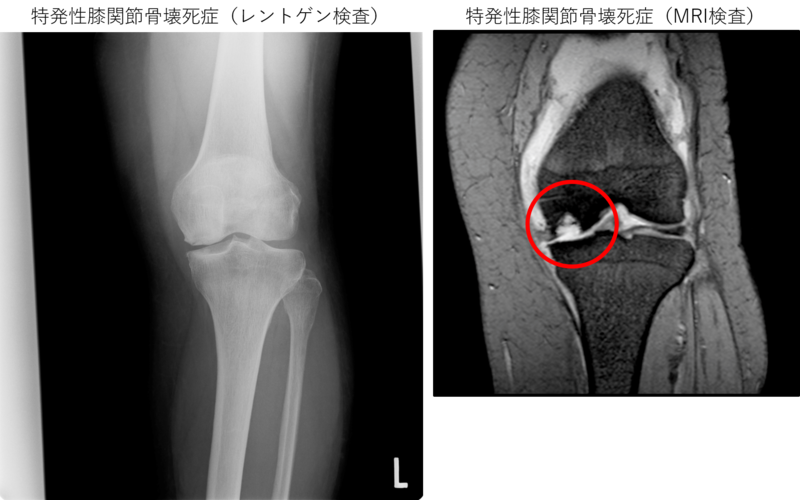

特発性膝関節骨壊死症の患者さんは、急激な強い痛みを感じて病院を受診されますが、レントゲン(X線)検査を行っても、原因は分からないことが多いです。強い痛みがあるにもかかわらず、変形性膝関節症のように軟骨が減っているなどの異常がみられないため、病気が発見されない可能性があります。

進行して骨の中が空洞になってくるとレントゲン検査で確認することができますが、骨の壊死が始まったばかりの初期の段階では、診断がつきにくいことが特徴です。

MRI検査では、骨の中の壊死している部分をはっきりと見ることができます。